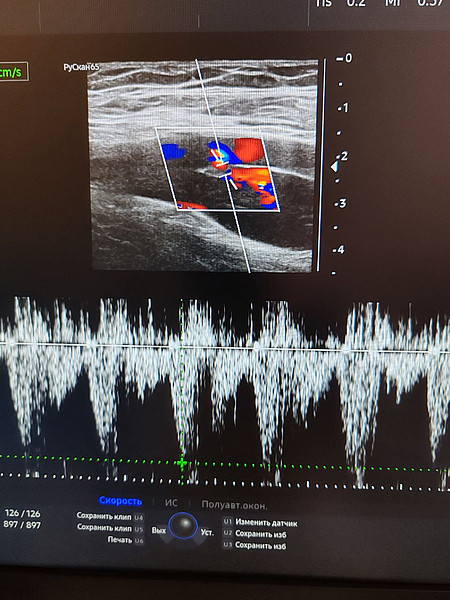

фистула 2.